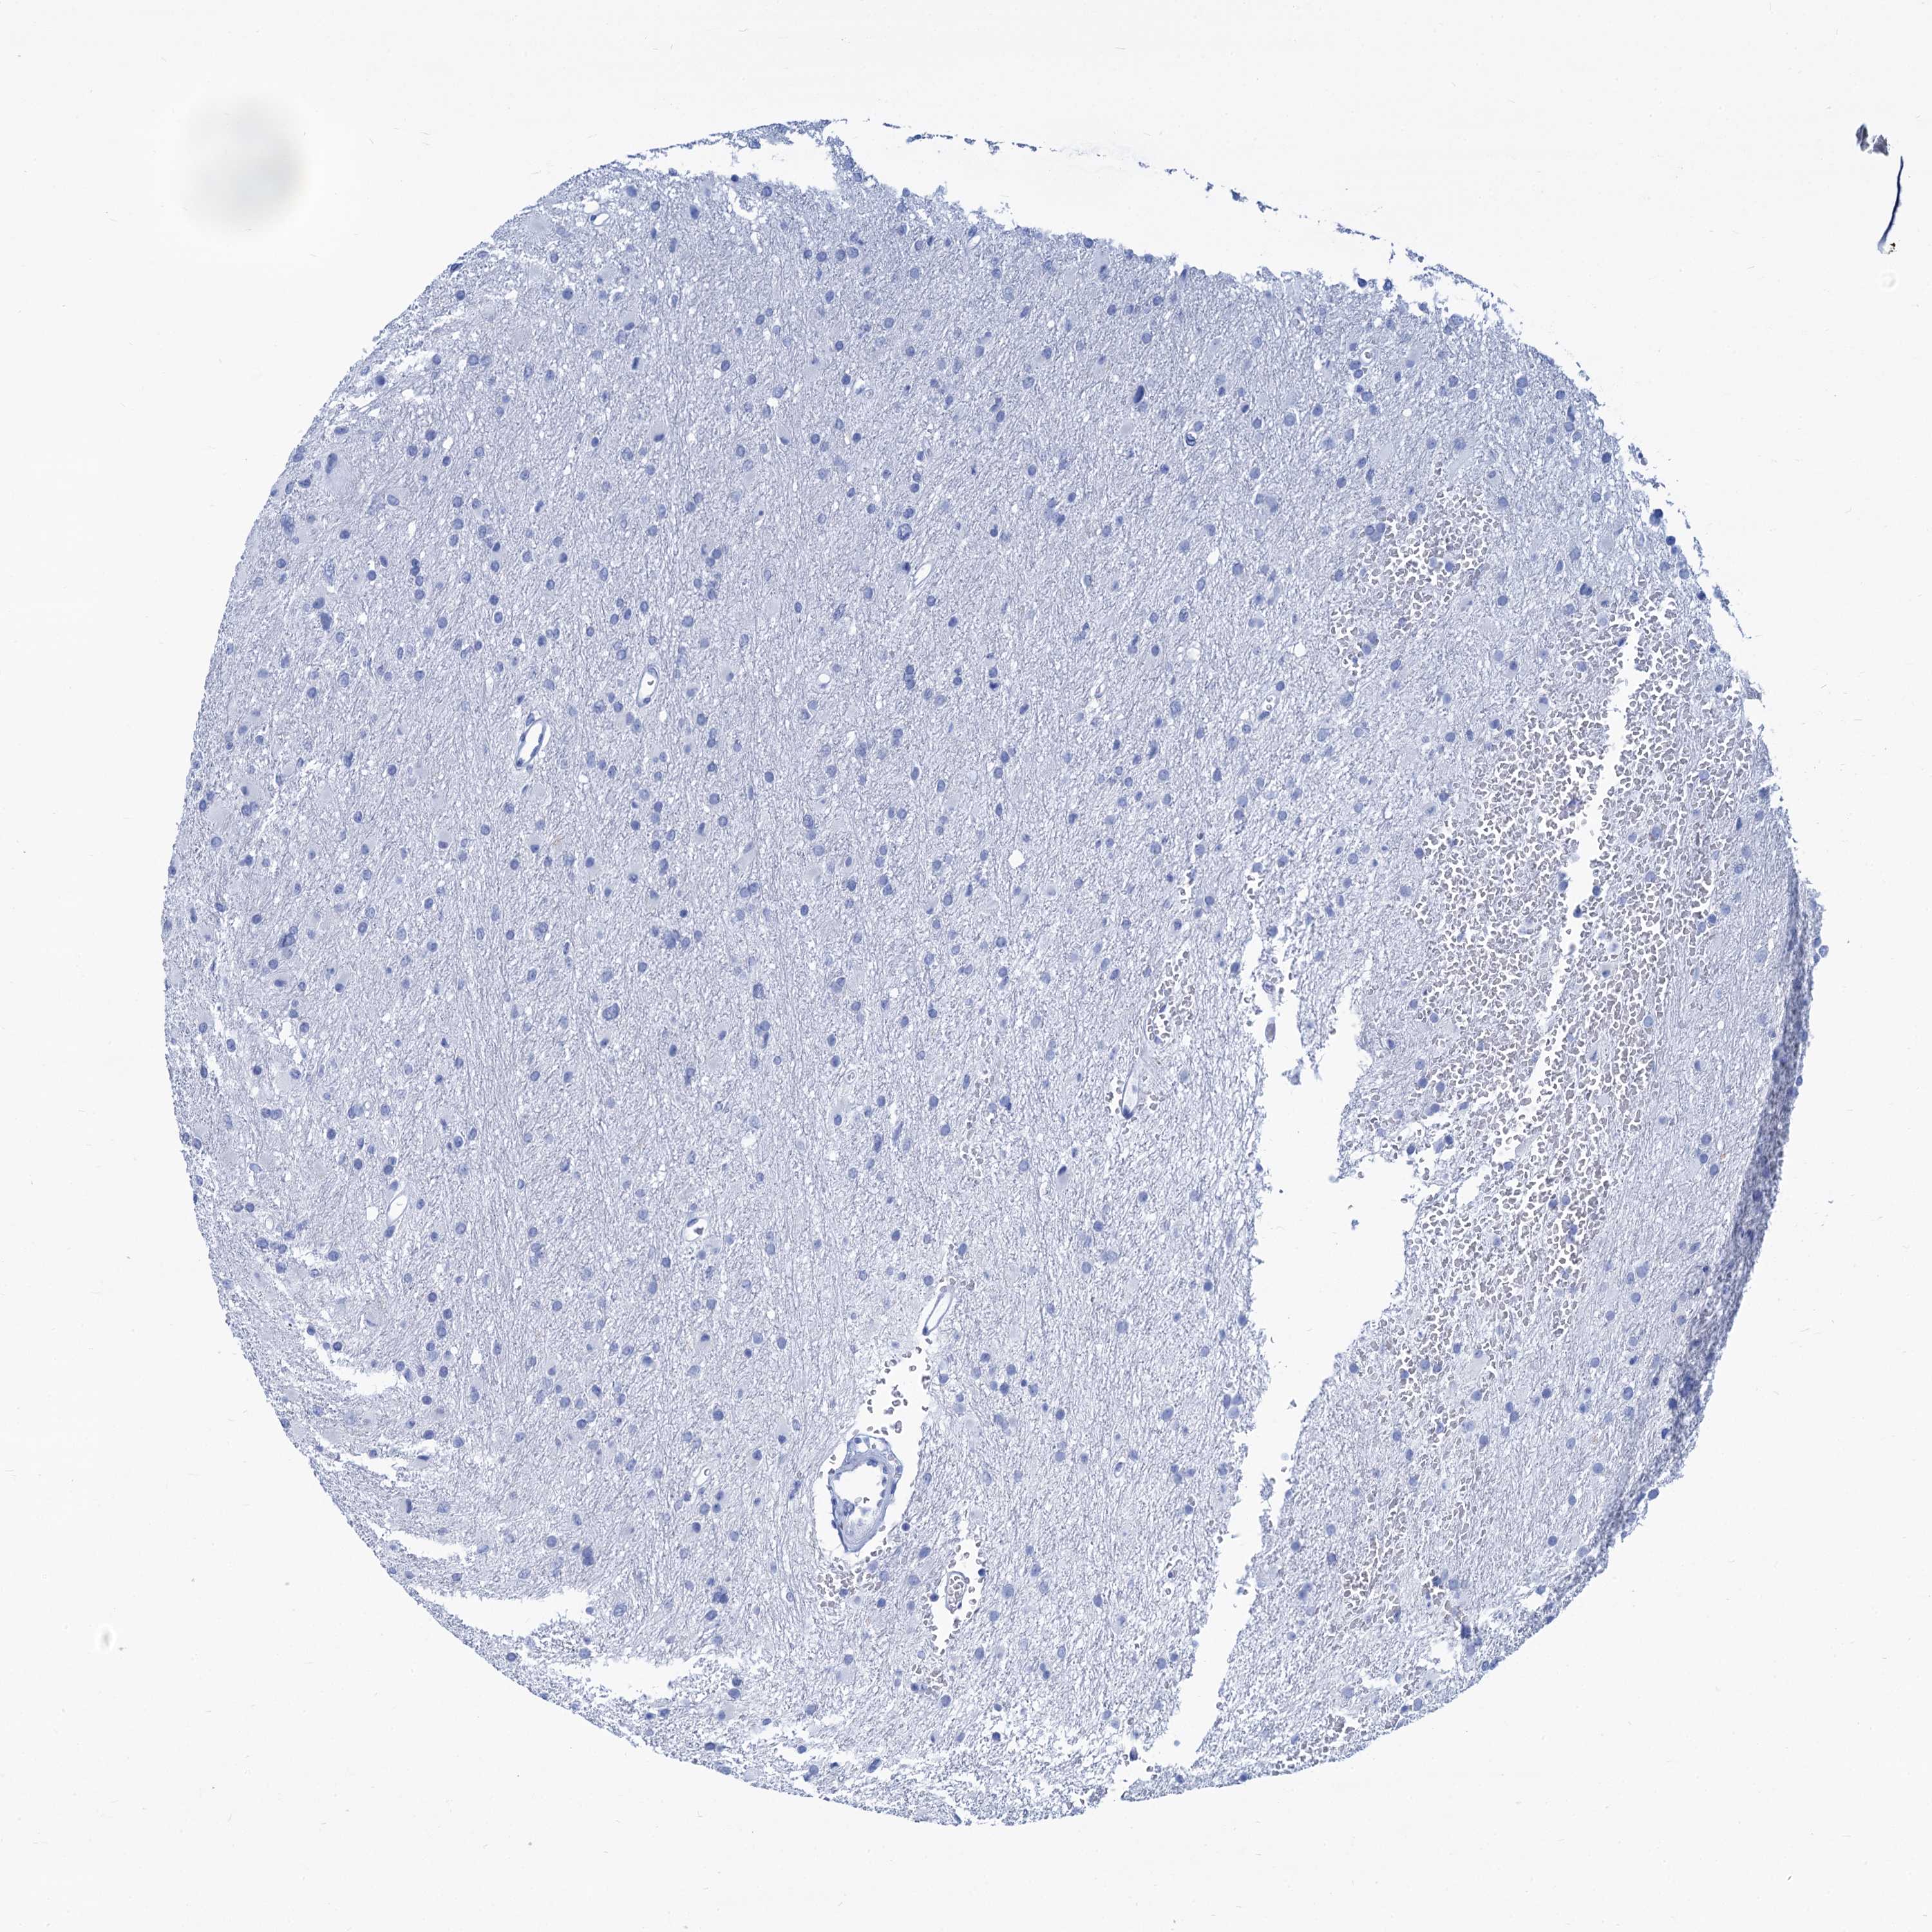

GLIOMA - Protein expressioni

A mouse-over function shows sample information and annotation data. Click on an image to view it in a full screen mode. Samples can be filtered based on level of antibody staining by selecting one or several of the following categories: high, medium, low and not detected. The assay and annotation is described here.

Note that samples used for immunohistochemistry by the Human Protein Atlas do not correspond to samples in the TCGA dataset.

Antibody stainingi

Antibody staining in the annotated cell types in the current human tissue is reported as not detected, low, medium, or high, based on conventional immunohistochemistry profiling in selected tissues. This score is based on the combination of the staining intensity and fraction of stained cells.

Each image is clickable and will lead to virtual microscopy that enables deeper exploration of all samples and also displays staining intensity scores, fraction scores and subcellular localization as well as patient and tissue information for each sample.

Antibody HPA040703

Antibody HPA047801

Staining

High

Medium

Low

Not detected

Intensity

Strong

Moderate

Weak

Negative

Quantity

>75%

75%-25%

<25%

None

Location

Nuclear

Cytoplasmic/membranous

Cytoplasmic/membranous,nuclear

Glioma, malignant, High grade

Glioma, malignant, Low grade